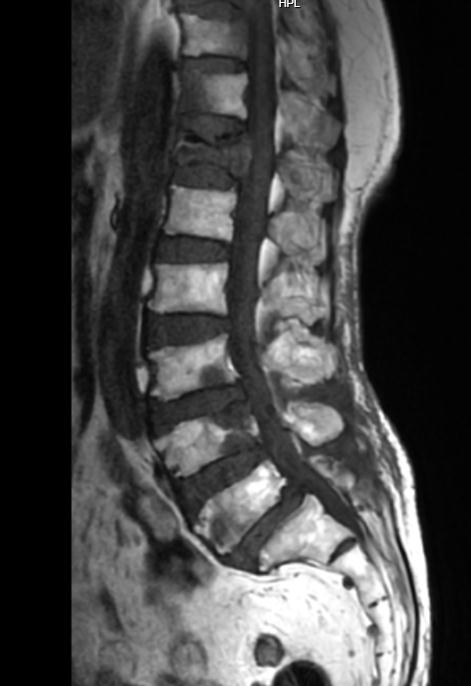

– Hình ảnh chụp cộng hưởng từ cột sống thắt lưng: Tổn thương đa ổ trong các thân đốt sống T9 đến T12, L2 đến L5, cuống sống T12 và L4 bên trái, cuống sống T9, T10, T12, L1, L4 có các ổ tổn thương giảm tín hiệu trên T1W, T2W, tăng tín hiệu trên STIR, sau tiêm ngấm thuốc mạnh, ổ lớn kích thước 35x28mm. Hình 4. Hình ảnh chụp cộng hưởng từ cột sống thắt lưng |